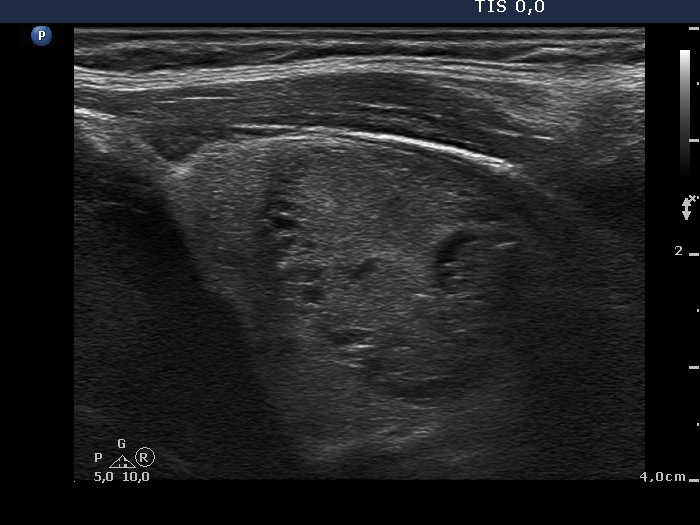

Ultrasonography. The right thyroid was significantly enlarged and contained multiple nodules with different echogenicity. The left thyroid was decreased in size and presented small insignificant lesions.

Scintigraphy disclosed an autonomously functioning nodule with a maximal diameter of 5 cm in the right lobe.